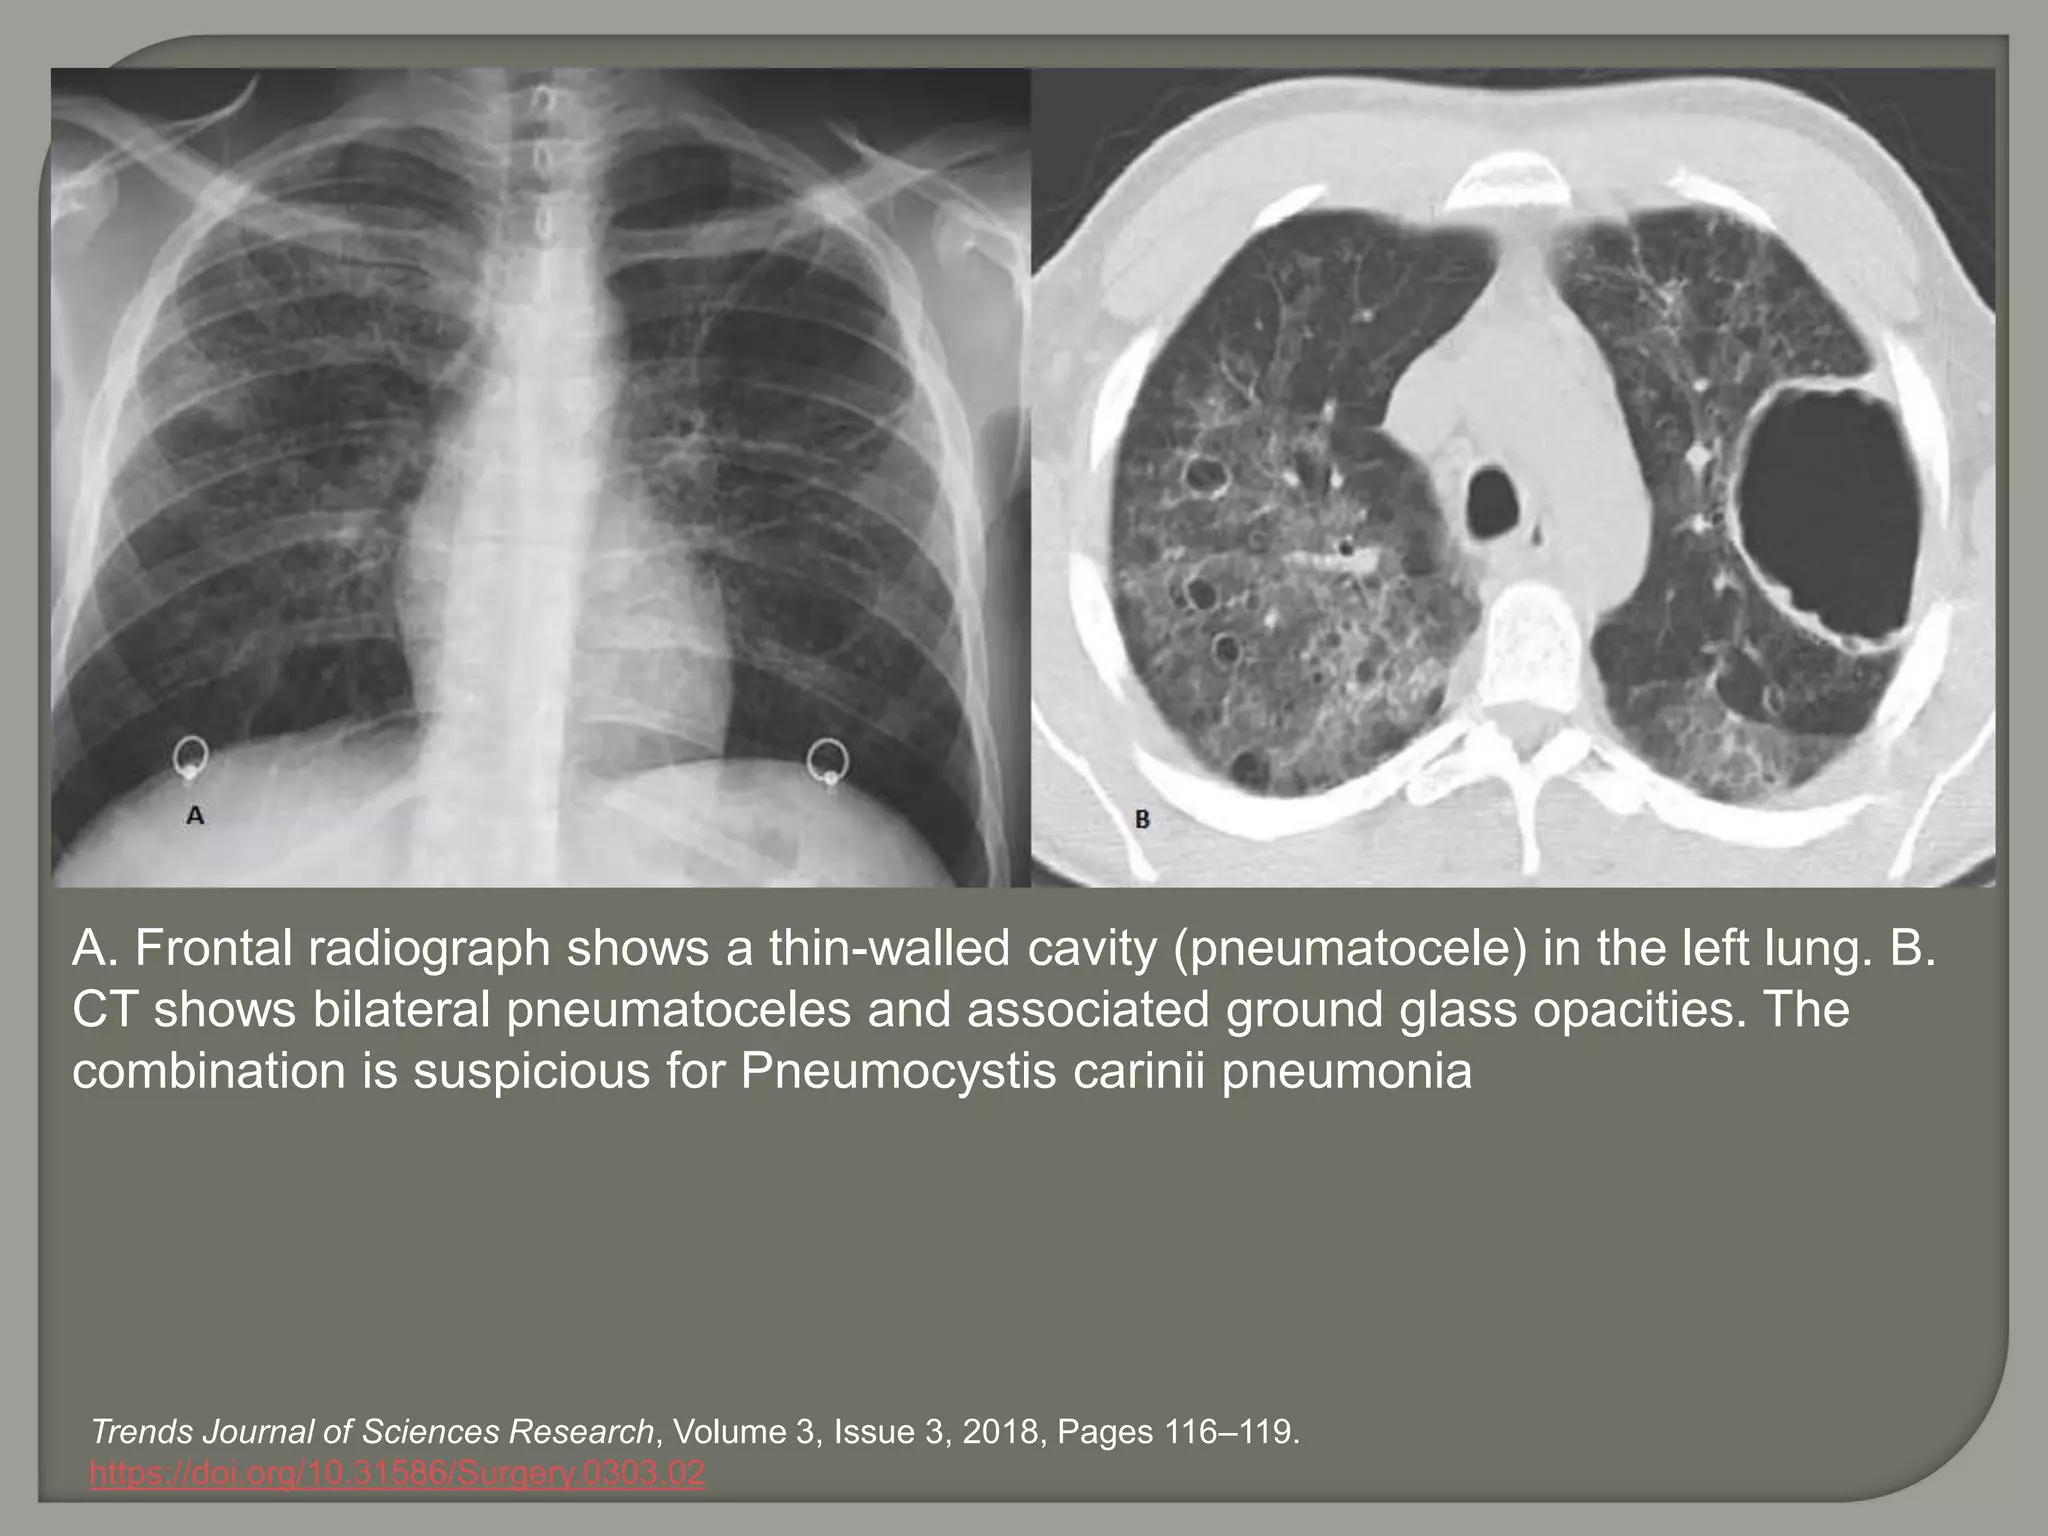

A. Frontal radiograph shows a thin-walled cavity (pneumatocele) in the left lung. B.

CT shows bilateral pneumatoceles and associated ground glass opacities. The

combination is suspicious for Pneumocystis carinii pneumonia

Trends Journal of Sciences Research, Volume 3, Issue 3, 2018, Pages 116–119.

https://doi.org/10.31586/Surgery.0303.02